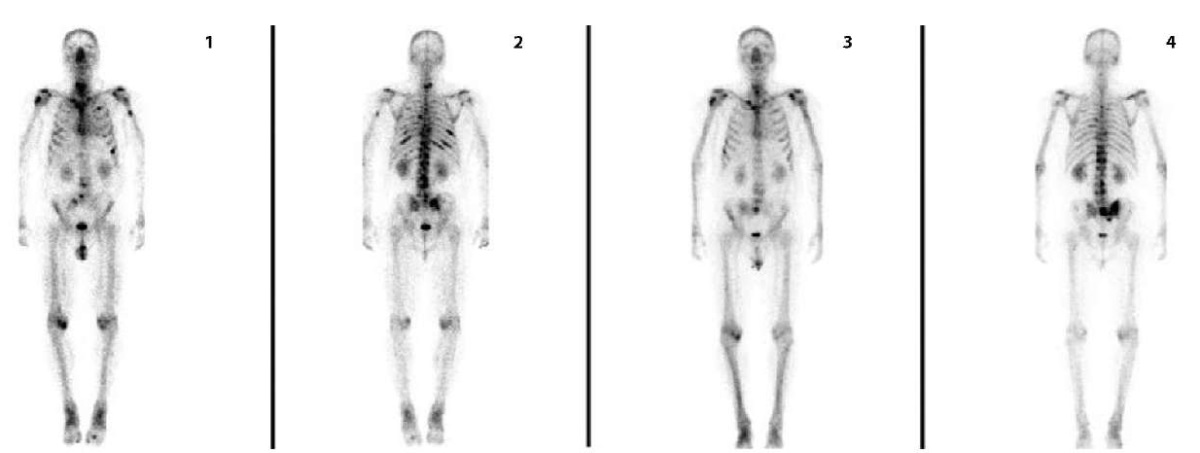

По данным остеосцинтиграфии у 8 пациентов (18,6 %) зафиксирован частичный метаболический ответ, сохраняющийся на протяжении 6–21 мес. после первого введения дихлорида радия-223. Стабилизация процесса наблюдается у 28 пациентов (65,1 %). Прогрессирование заболевания зафиксировано в 7 случаях (16,3 %), среди них во 2-й линии — у 1 пациента (2,3 %), в 3-й линии — у 3 пациентов (7 %), в 4-й линии — у 3-й пациентов (7 %). Наиболее показательная динамика наблюдалась у пациентов, имеющих менее 20 вторичных костных очагов (рис. 4).

Рисунок 4. Пациент Б., 57 лет, с мКРРПЖ. По поводу метастатической ацинарной аденокарциномы (Глисон 4+3) проводилась ранее дистанционная лучевая терапия, курсы химиотерапии таксанами и гормональными препаратами с последующим развитием кастрационной резистентности. Проведен полный курс РНТ. Представлены первичные (1–2) и контрольные (3–4) сцинтиграммы: отмечается разнонаправленная динамика в виде снижения фиксации РФП в большинстве вторичных костных очагов, повышение фиксации РФП в левой подвздошной кости. В последующем было выявлено прогрессирование заболевания в виде метастазирования в регионарные лимфатические узлы — пациент в процессе терапии лютецием-177

Figure 4. Patient B., 57 years old, with castration-resistant prostate cancer. For metastatic acinar adenocarcinoma (Gleason 4+3), external beam radiation therapy, courses of chemotherapy with taxanes and hormonal drugs with subsequent development of castration resistance were previously performed. A full course of radionuclide therapy was performed. Primary (1–2) and control (3–4) scintigrams are presented: multidirectional dynamics are noted in the form of a decrease in the fixation of radiopharmaceutical agent in most secondary bone foci, an increase in the fixation of radiopharmaceutical agent in the left iliac bone. Subsequently, disease progression was detected in the form of metastasis to regional lymph nodes. The patient is undergoing lutetium-177 therapy